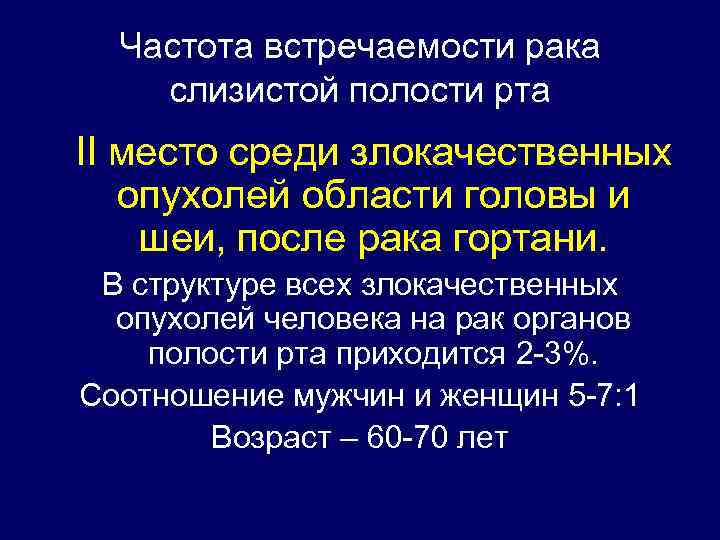

Частота встречаемости рака слизистой полости рта II место среди злокачественных опухолей области головы и шеи, после рака гортани. В структуре всех злокачественных опухолей человека на рак органов полости рта приходится 2 -3%. Соотношение мужчин и женщин 5 -7: 1 Возраст – 60 -70 лет

Частота встречаемости рака слизистой полости рта II место среди злокачественных опухолей области головы и шеи, после рака гортани. В структуре всех злокачественных опухолей человека на рак органов полости рта приходится 2 -3%. Соотношение мужчин и женщин 5 -7: 1 Возраст – 60 -70 лет